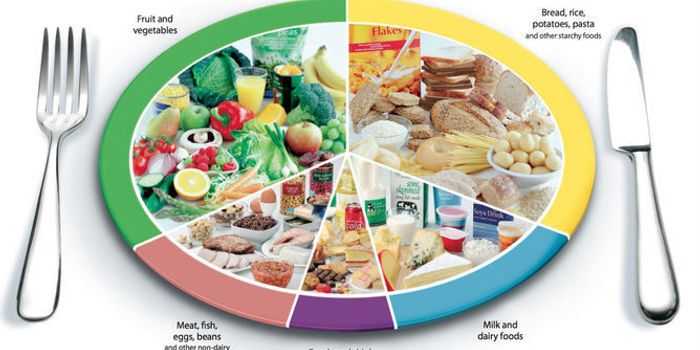

MAR 30, 2015Health & MedicineMeet the Eatwell Plate. The Eatwell plate is the UK government's official food guide about which foods we should eat to ...